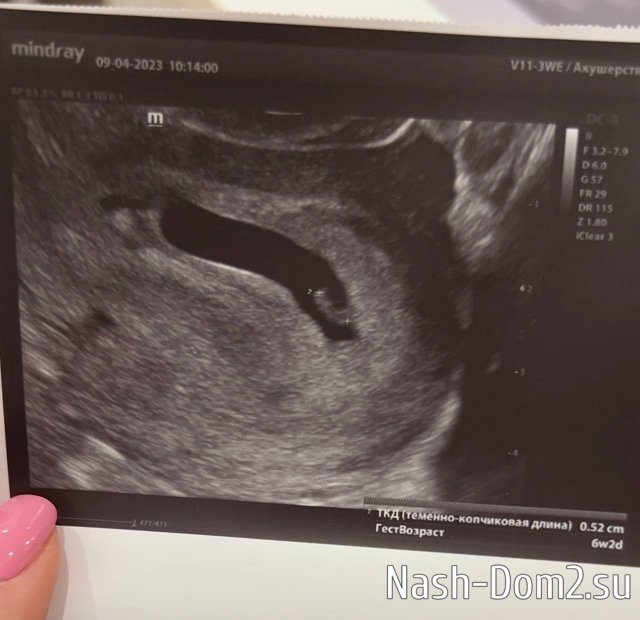

Вам доброе утро от моего головастика!

Сделали узи- нам уже почти 7 недель ❤

Вчера проснулась от дикой боли внизу живота.. сегодня выяснилось, что это связано с тонусом((

Пора расслабляться…